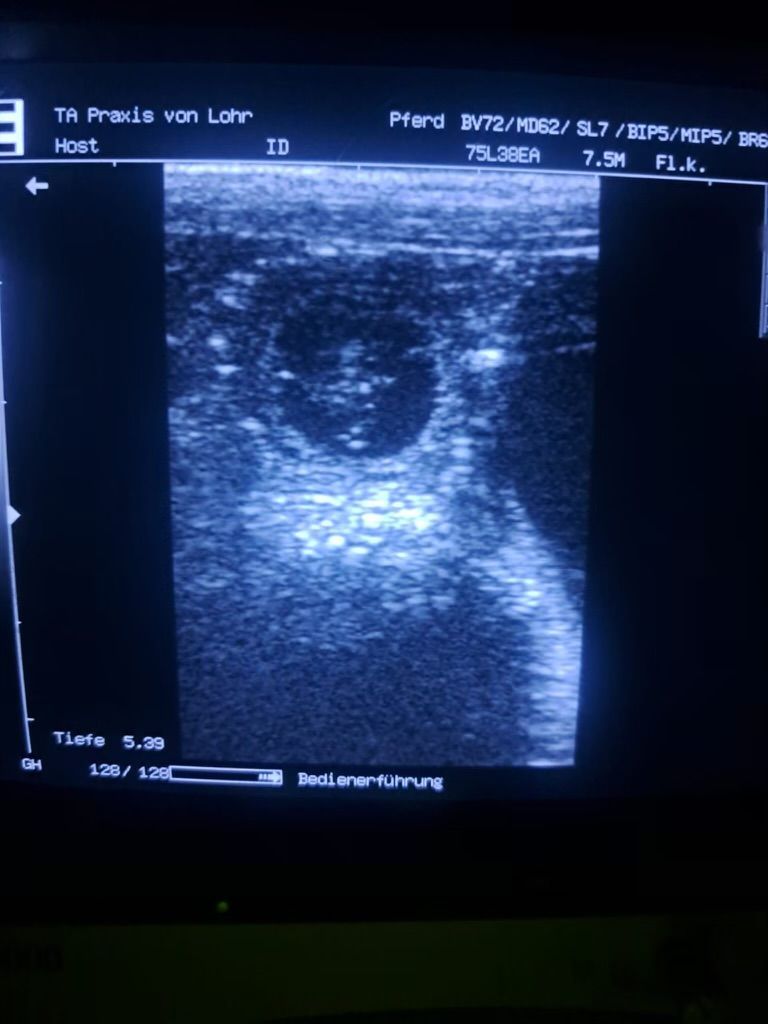

Riley ist schwanger

Nun ist es bestätigt und es ist sicher

Riley ist tragend und die Welpen werden Anfang April erwartet.